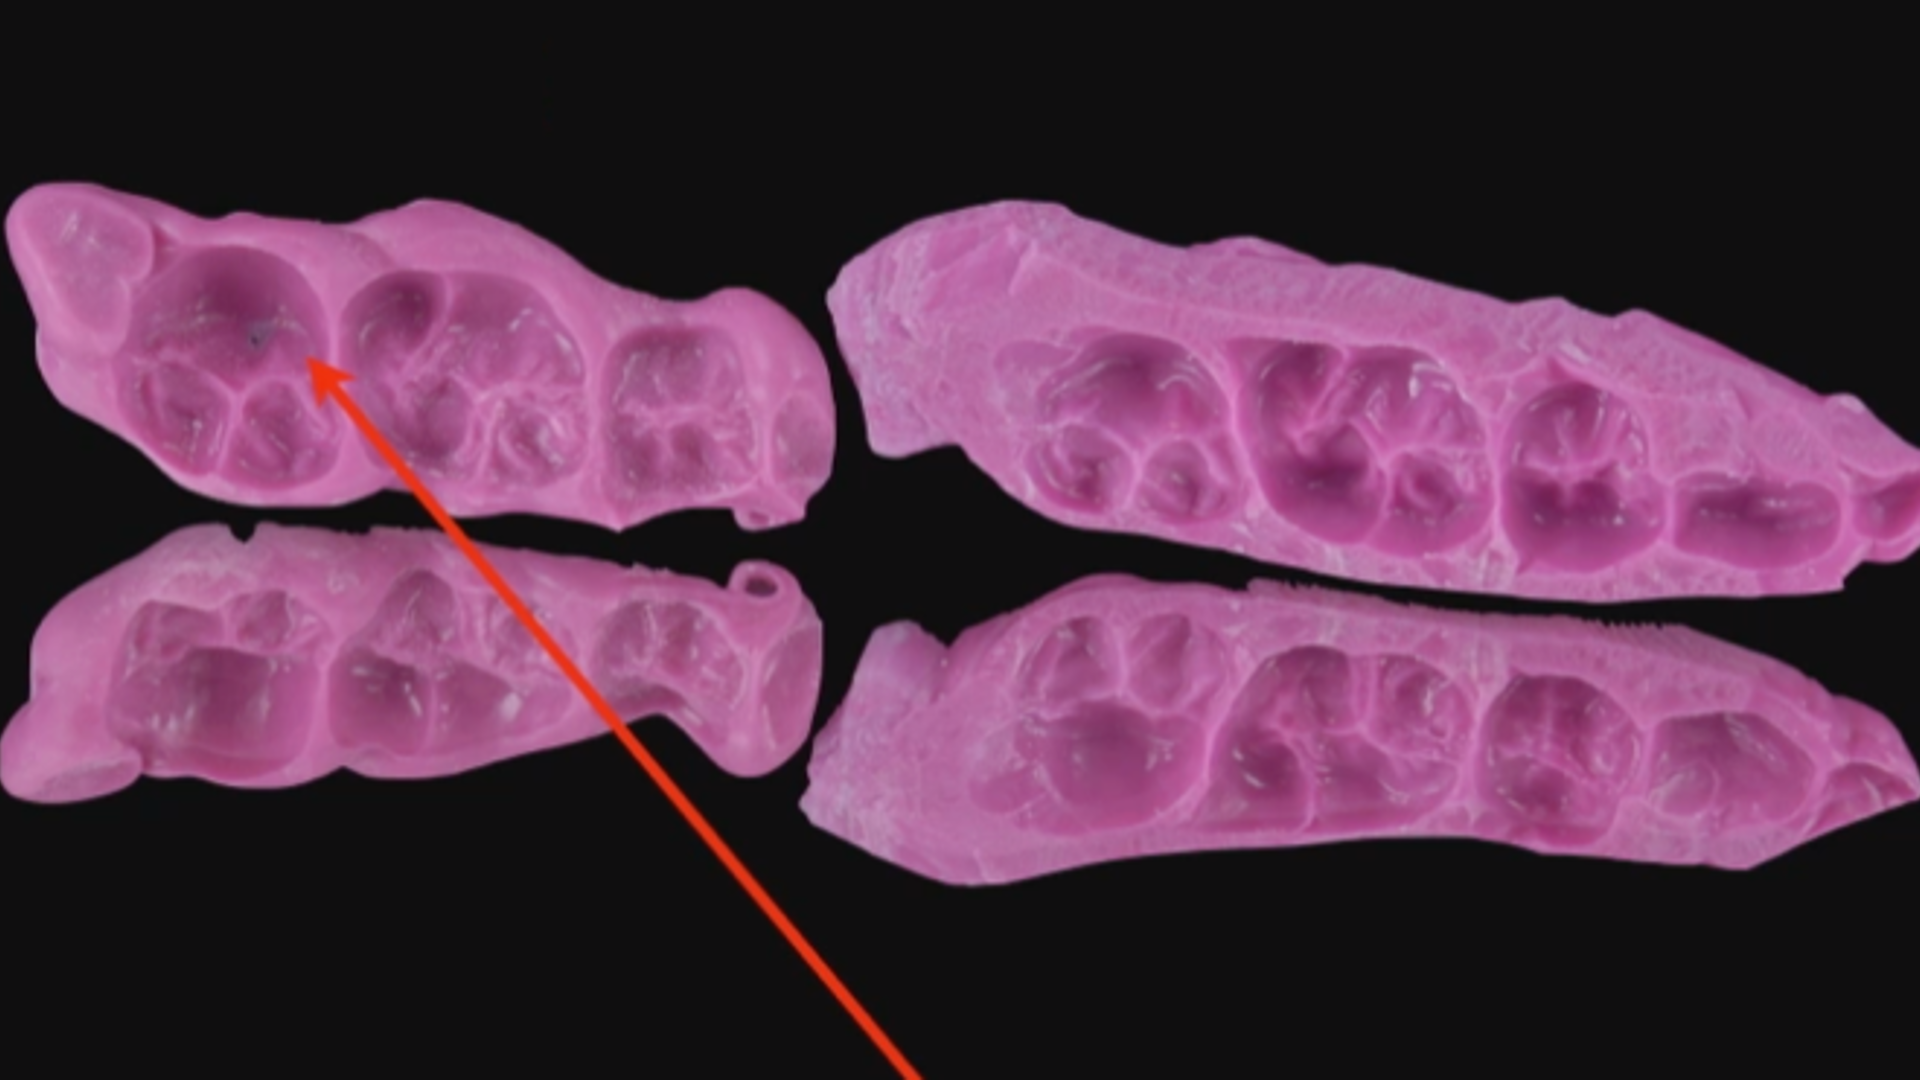

MIPP 0: clinical cases and No-prep veneers procedures

Clinical case - MIPP 1: conventional buccal veneers procedures

Clinical case - MIPP 3: occlusal parameters alteration

Clinical case - MIPP 3 (part 1 of 3): treatment planning and data collection

Clinical case - MIPP 3 (part 2 of 3): dental impression and provisional management

Clinical case - MIPP 3 (part 3 of 3): finalisation, restorations construction and cementation

MIPP 2: the new concept behind Full-Veneers to optimise aesthetics and functionality

MIPP 2B: clinical case of Full-Veneers in openbite with preserved enamel tooth structure

MIPP 2: MIPP 2A and MIPP 2B combined technique